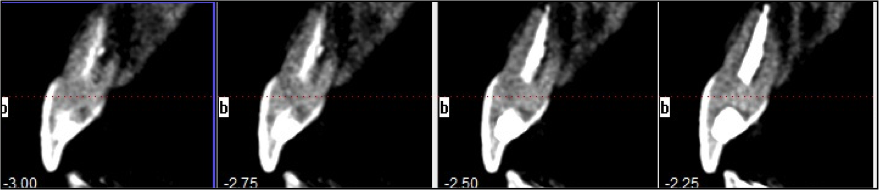

Tooth Injury comprises a group of clinical conditions that can have the separation or breakage of the tooth and its surrounding tissues. A case of multiple concomitant dental trauma is reported. In 2004, a female patient, 11 years old, visited the dental office a half hour after a dental trauma caused by a fall in the pool. She complained of mild discomfort in the tooth 11; in a clinical analysis, it was partially displaced from its socket and showed grade 2 mobility; in a radiographic analysis, the tooth showed an increase in the periodontal ligament space, a diagnosis of extrusive luxation. The adjacent teeth 21 and 22, presented subgingival bleeding, diagnosed with subluxation. After preparing the treatment plan, clinical approach consisted of manual reduction of the tooth 11 and non-rigid splint of affected teeth. The patient received a prescription of antibiotic and anti-inflammatory. After 15 days, the splint was removed and the teeth 11, 21 and 22 showed pulpal sensibility, maintaining the same results for 4 months. In the 4th month, tooth 11 was diagnosed with pulp necrosis, thus requiring endodontic treatment. After 10 years, teeth were asymptomatic, with a slight color change in tooth 11; the cone beam scan indicated root resorption in the apical third of the three elements and the presence of dystrophic calcification of teeth 21 and 22. In conclusion, the injured teeth remain in function with relevant follow-up period, highlighting the search for a response, upon the purpose of the study.